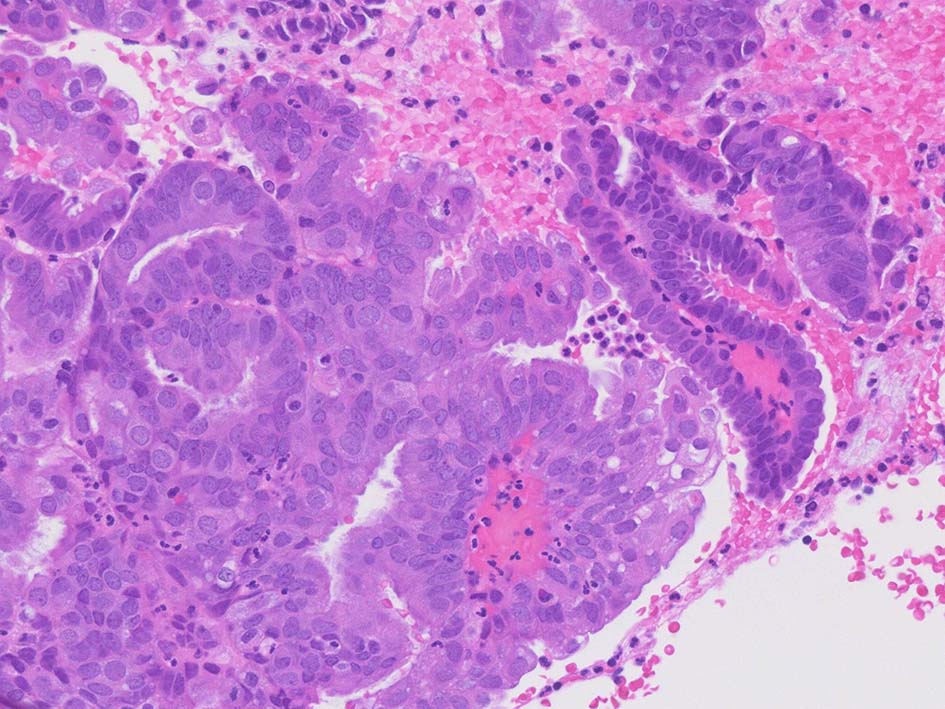

INI1-tumor.jpg INI1-deficient tumor.jpg

Malignant rhabdoid tumor